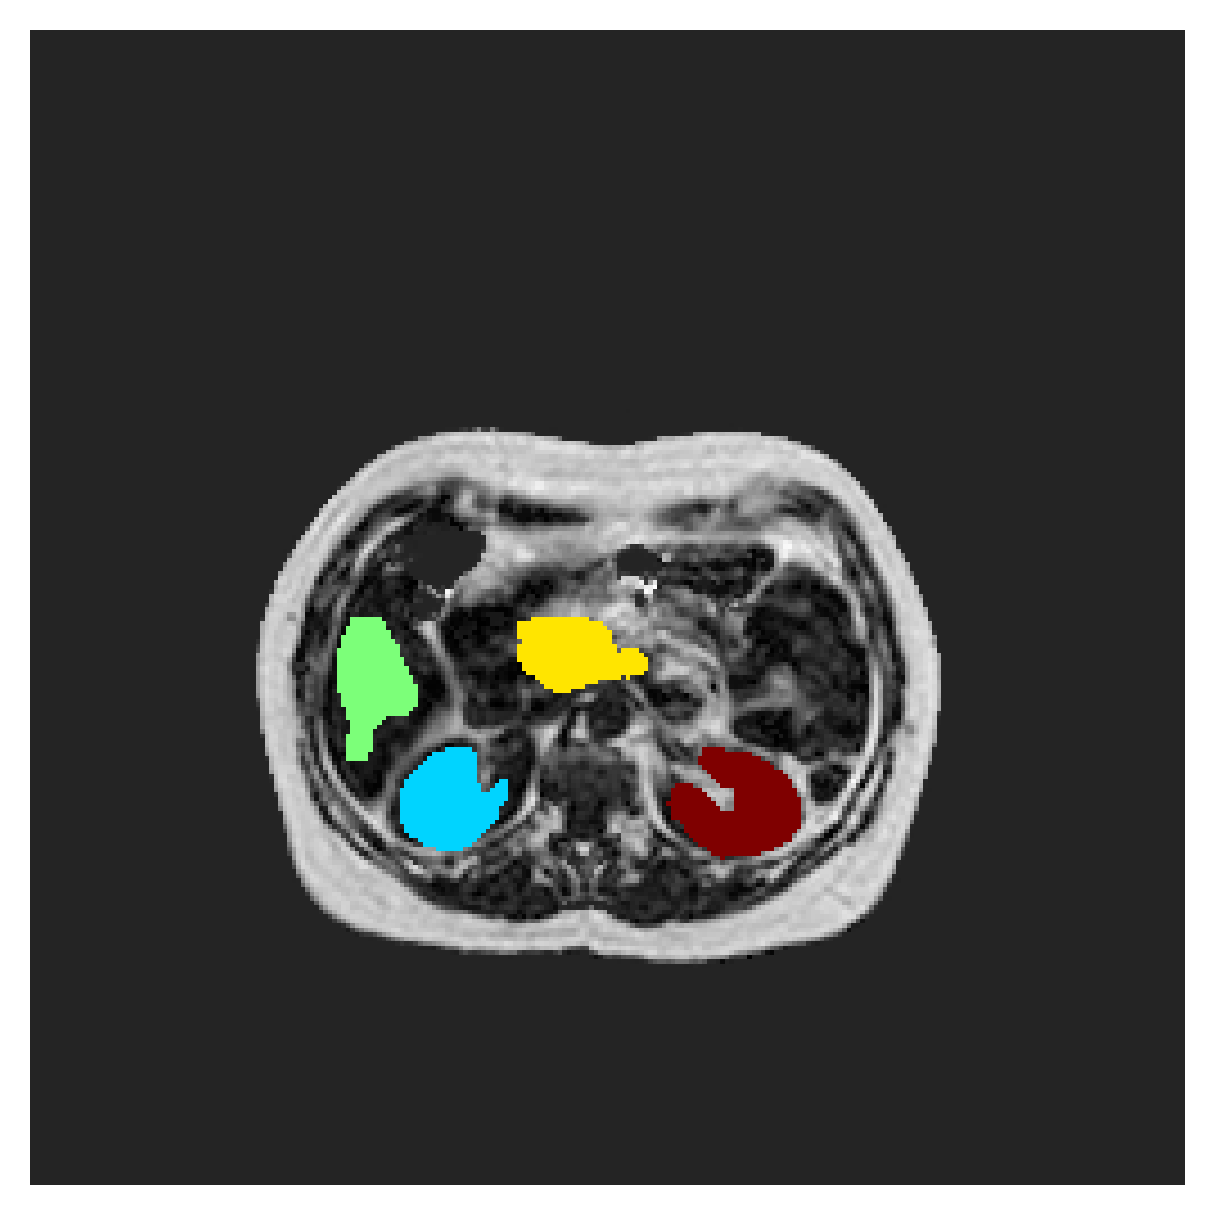

POEM

The Prospective investigation of Obesity, ENergy production and Metabolism (POEM) is a local (not currently publicly available; PI: L. Lind, see [22] for details) cohort of whole-body fat/water separated MR images. Full annotations of the liver, kidneys, bladder, pancreas and spleen are available for 50 subjects, providing a challenging segmentation dataset with heavily imbalanced classes of varying shapes. The resolution of the data is anisotropic, with reconstructed voxel size of in left-right, anterior-posterior and foot-head directions, respectively. For additional technical details regarding the acquisition and specifications of the images see [22].

The images contain two channels, one for water and one for fat content. For training, we normalize the volumes (per channel) and use 2D slices in the coronal plane, sized . The weak annotations are created synthetically, following the same procedure as described for the ACDC dataset.

5.2 Abdominal organ segmentation

Using 2D distance maps

In Table 3, the average DSC and HD95 results are shown (both using 2D and 3D distance maps) for the task of abdominal organ segmentation in POEM data (for boxplots see figures 8 and 9). We see that training with and (with distances calculated on 2D slices) performs comparably, while using and produces lower scores in both DSC and HD95 metric. On this dataset, the CRF-loss is able to compete with the boundary loss-based training strategies, even outperforming them on most classes. Most notably, all models trained with boundary loss appear to have a hard time segmenting the liver. We hypothesize this may be due to extremely severe class imbalance, as the liver covers a very large area compared to the rest of the classes. It is thus also more strongly affected by undersegmentations.

Using 3D distance maps

Inspecting the values of training with on distance maps computed in 3D from Table 3, we notice that the results generally improve over values achieved by using 2D distance maps. Most notable decreases are visible in HD95 values, as using volume-calculated distance maps provides more global information and additionally penalizes spatially unreasonable segmentations. The methods based on are now able to compete with the CRF-loss, in particular the one.

5.2.1 Qualitative comparison

In Figure 11 and 12 we show the same random slices in cases of calculating the boundary loss on 2D- and 3D-based distances, respectively. Comparing the two figures again indicates that the intensity-aware distances offer most improvement when calculated in 3D over 2D. The exception here is the MBD, which seems to even slightly degrade for most classes.